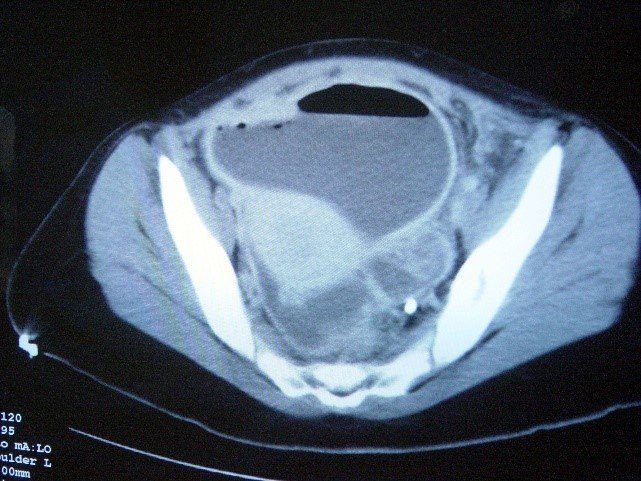

- KT peritonitin səbəbini müəyyənləşdimədə standart müayinədir. Qarında maye, sərbəst hava,± kontrast ekstravazasiyası, orqan patologiyaları peritonitin xarakterik əlamətləridir.

- USM/KT – də qarında maye, hava, kontrast ekstravazasiyası və orqan patologiyaları.